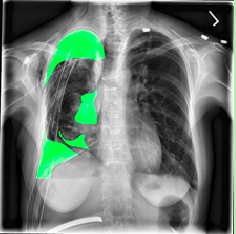

Our model is showing promising results as we can see the masks predicted by the model in figures 8(a) 8(b) 8(c) match closly to the real annotation. Our Dice score and IoU score are 84.3 and 82.6 respectively. Both of these metrics are used to indicate the similarity between images. And in figures 9(a) 9(b) 9(c) 10(a) 10(b) 10(c) we can see the results are very good and insightful. Both Dice score and IoU indicates that model is strong. Dice score and IoU both are positively correlated. It means if one say a model is strong then other will also support the decision. Using ResNet as backbone in U-net architecture helps converse the model fast and improves the results. The implementation is also easy in Keras. There are other metrics also but these metrics are considered best to test similarity between two images.

Refer to caption

(a) Input image

(b) Image with predicted mask

(c) Real Annotation

Figure 8: Patient 1